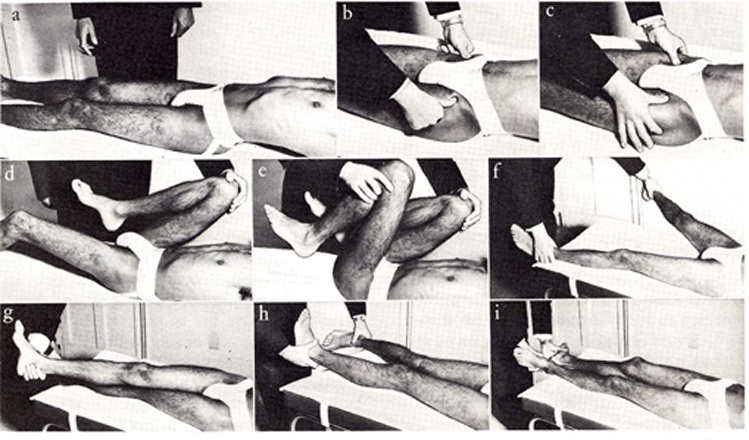

Abbildung: Ohne reproduzierbare Anhaltspunkte bezüglich Fussstellung und den Ausweichhaltungen wird eine Person in der entspannten Körperhaltung bebildert. |

Abbildung: Leider fehlen die erwähnten Angaben, |

Was kann eine solche Aufnahme ohne Muskelspannung aufzeigen? Über die Knieentlastung verändern sich Hüftgelenk- und Rückgrat-Stellungen. Wie kann somit eine Stellungsveränderung z.B. über eine einseitige Knieblockade, oder eine Stellungsveränderung der Beinschenkelwinkel zum Becken, eine schiefe Beckenebene festgestellt werden, die eventuell Gelenk oder Rückenbeschwerden verursachen können. Weiter verändert sich die Rückgrat-Stellung. Wie werden dabei Hohl- und Flachrücken im Zusammenhang beurteilt? |

Knie-Unterlage zur Entlastung Ein Körper ohne Belastung stellt wohl ein optisch genaues Bild dar, kann jedoch keine Auskunft über einen fehlbelasteten Körper geben. Dabei fehlen auch folgende Fragen: Haben Sie Angst, Angstinformation erhalten Alle diese |